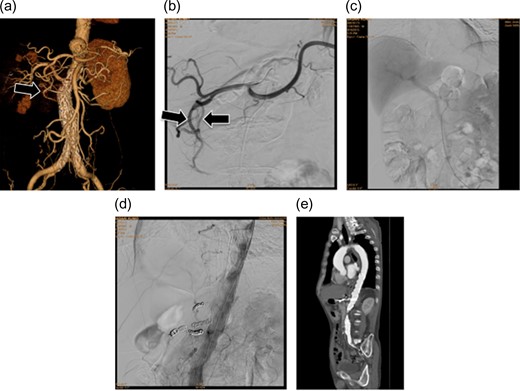

(a and b) Preoperative contrast-eCT. (c and d) eCT performed on postoperative day 13. A cyst is seen on the pancreatic tail (black arrow), while no contrast effect is seen in the spleen (white arrow). (e and f) CT performed on postoperative day 21. The pancreatic cyst has started to shrink. Part of the spleen becoming necrotic does not conflict with an etiology of ischemia due to embolization of the splenic artery.

Intravenous hydration was initiated. His leukocyte count rose to 31 290 µl–1 on postoperative day 8, after which it gradually improved, normalizing on postoperative day 21. Similarly, CRP peaked at 24.55 mg/dl on postoperative day 7, after which it gradually improved, plateauing at around 2.0 mg/dl.

Follow-up eCT on postoperative day 13 showed expanded necrotic and cystic areas compared to immediately after onset. Infected necrosis was suspected. Meropenem 1.0 g/day and a protease inhibitor, gabexate mesilate 2500 mg/day, were administered. eCT on postoperative day 20 showed shrinkage of the pancreatic necrosis and cyst.

The patient did not have preoperative risk factors for pancreatitis. Additionally, CT images taken at the arterial and late phases (180 s) did not show a contrast effect in the splenic artery distal to the embolism or the spleen. Pancreatitis occurred immediately after the arteries perfusing the pancreas were surgically embolized. Therefore, we diagnosed pancreatitis due to reduced pancreatic blood flow secondary to embolization (Fig. 2).